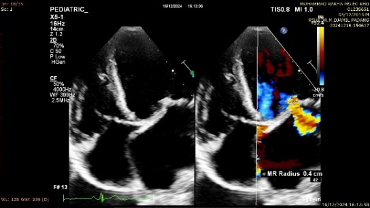

Coexistence of Infective Endocarditis and Recurrent Acute Rheumatic Fever: A Case Report

Kino Kino, Didik Hariyanto, Harben Fernando, Indra Fahlevi

29-34

DOI: https://doi.org/10.63918/fhr.v2.n2.p29-34.2025